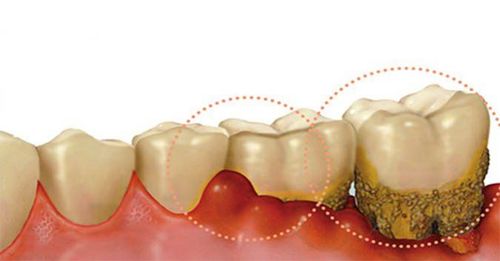

Các triệu chứng cảnh báo viêm lợi

Bệnh viêm lợi là một chứng bệnh phổ biến trên toàn thế giới, cả người lớn và trẻ nhỏ đều là đối tượng dễ mắc phải. Viêm lợi không chỉ gây ra cảm giác đau đớn, nó còn ảnh hưởng đến sinh hoạt và giao tiếp của người bệnh.